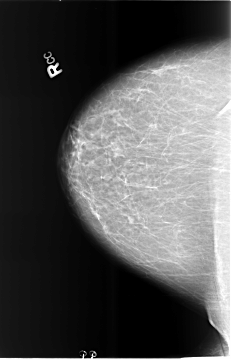

B_3473_1.RIGHT_MLO

RIGHT_CC LINES 5736 PIXELS_PER_LINE 3688 BITS_PER_PIXEL 12 RESOLUTION 50 NON_OVERLAY

RIGHT_MLO LINES 5712 PIXELS_PER_LINE 3992 BITS_PER_PIXEL 12 RESOLUTION 50 NON_OVERLAY